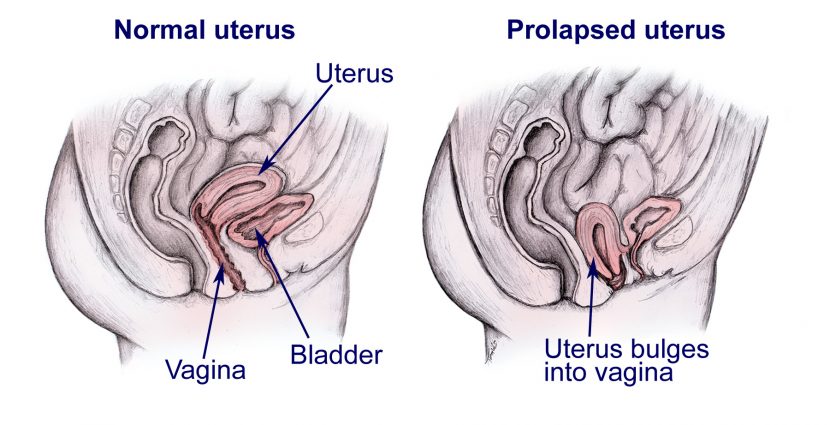

দড়িলাফে কী মেয়েদের জরায়ু ক্ষতিগ্রস্থ হয়?

0 SHARES Share Tweet দড়িলাফে কী মেয়েদের জরায়ু ক্ষতিগ্রস্থ হয়, এ নিয়ে আমাদের আজকের আলোচনা। তার পূর্বে কিছু কথা বলে নেই।...